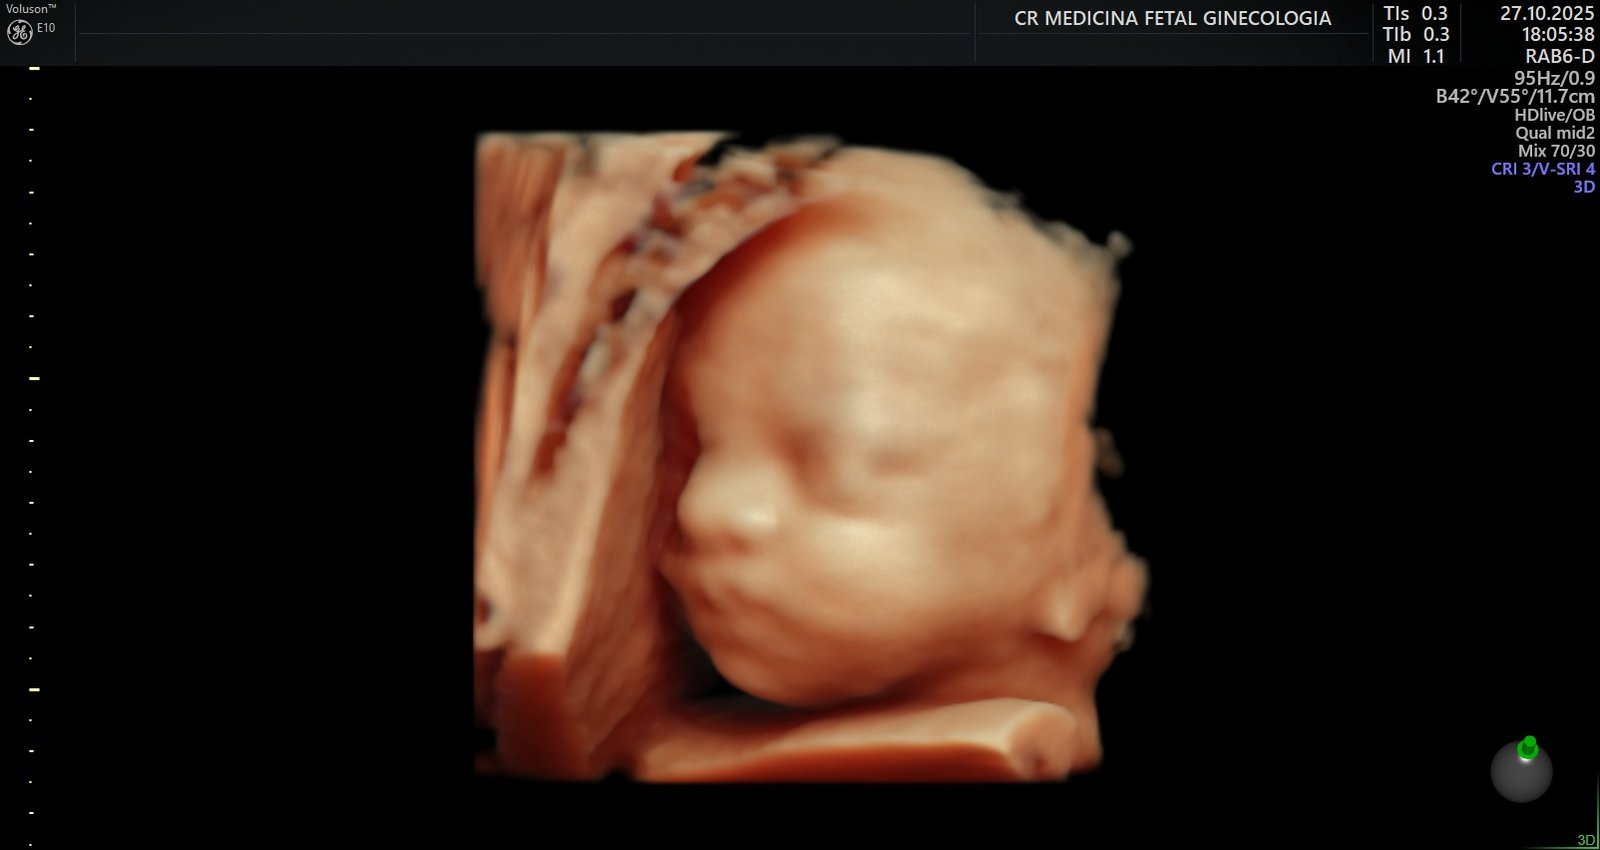

Ultrassonografia 3D e 4D: Permite visualizar o bebê em alta definição, em tempo real, em qualquer idade gestacional, proporcionando um vínculo ainda maior entre a família e o bebê.

Ultrassonografia obstétrica morfológica do segundo trimestre: Realizado entre a 20ª e a 24ª semana, analisa minuciosamente a anatomia fetal, incluindo coração, cérebro, rins, membros e outros órgãos vitais, além do cálculo de risco para parto prematuro através da medida de colo e nova avaliação de artérias uterinas com o Doppler.